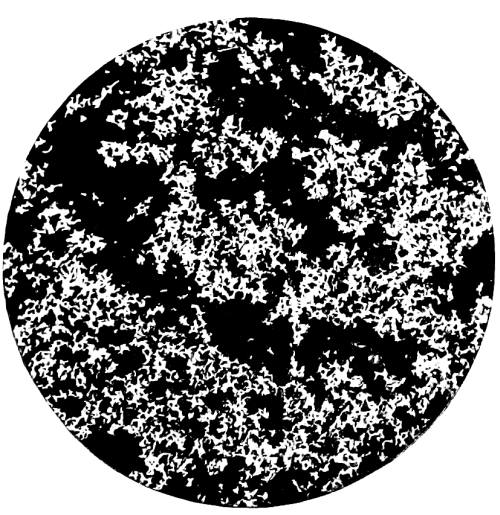

30. Photo-micrograph of Sublimate of Arsenious Acid obtained by Reinsch‘s Process 284